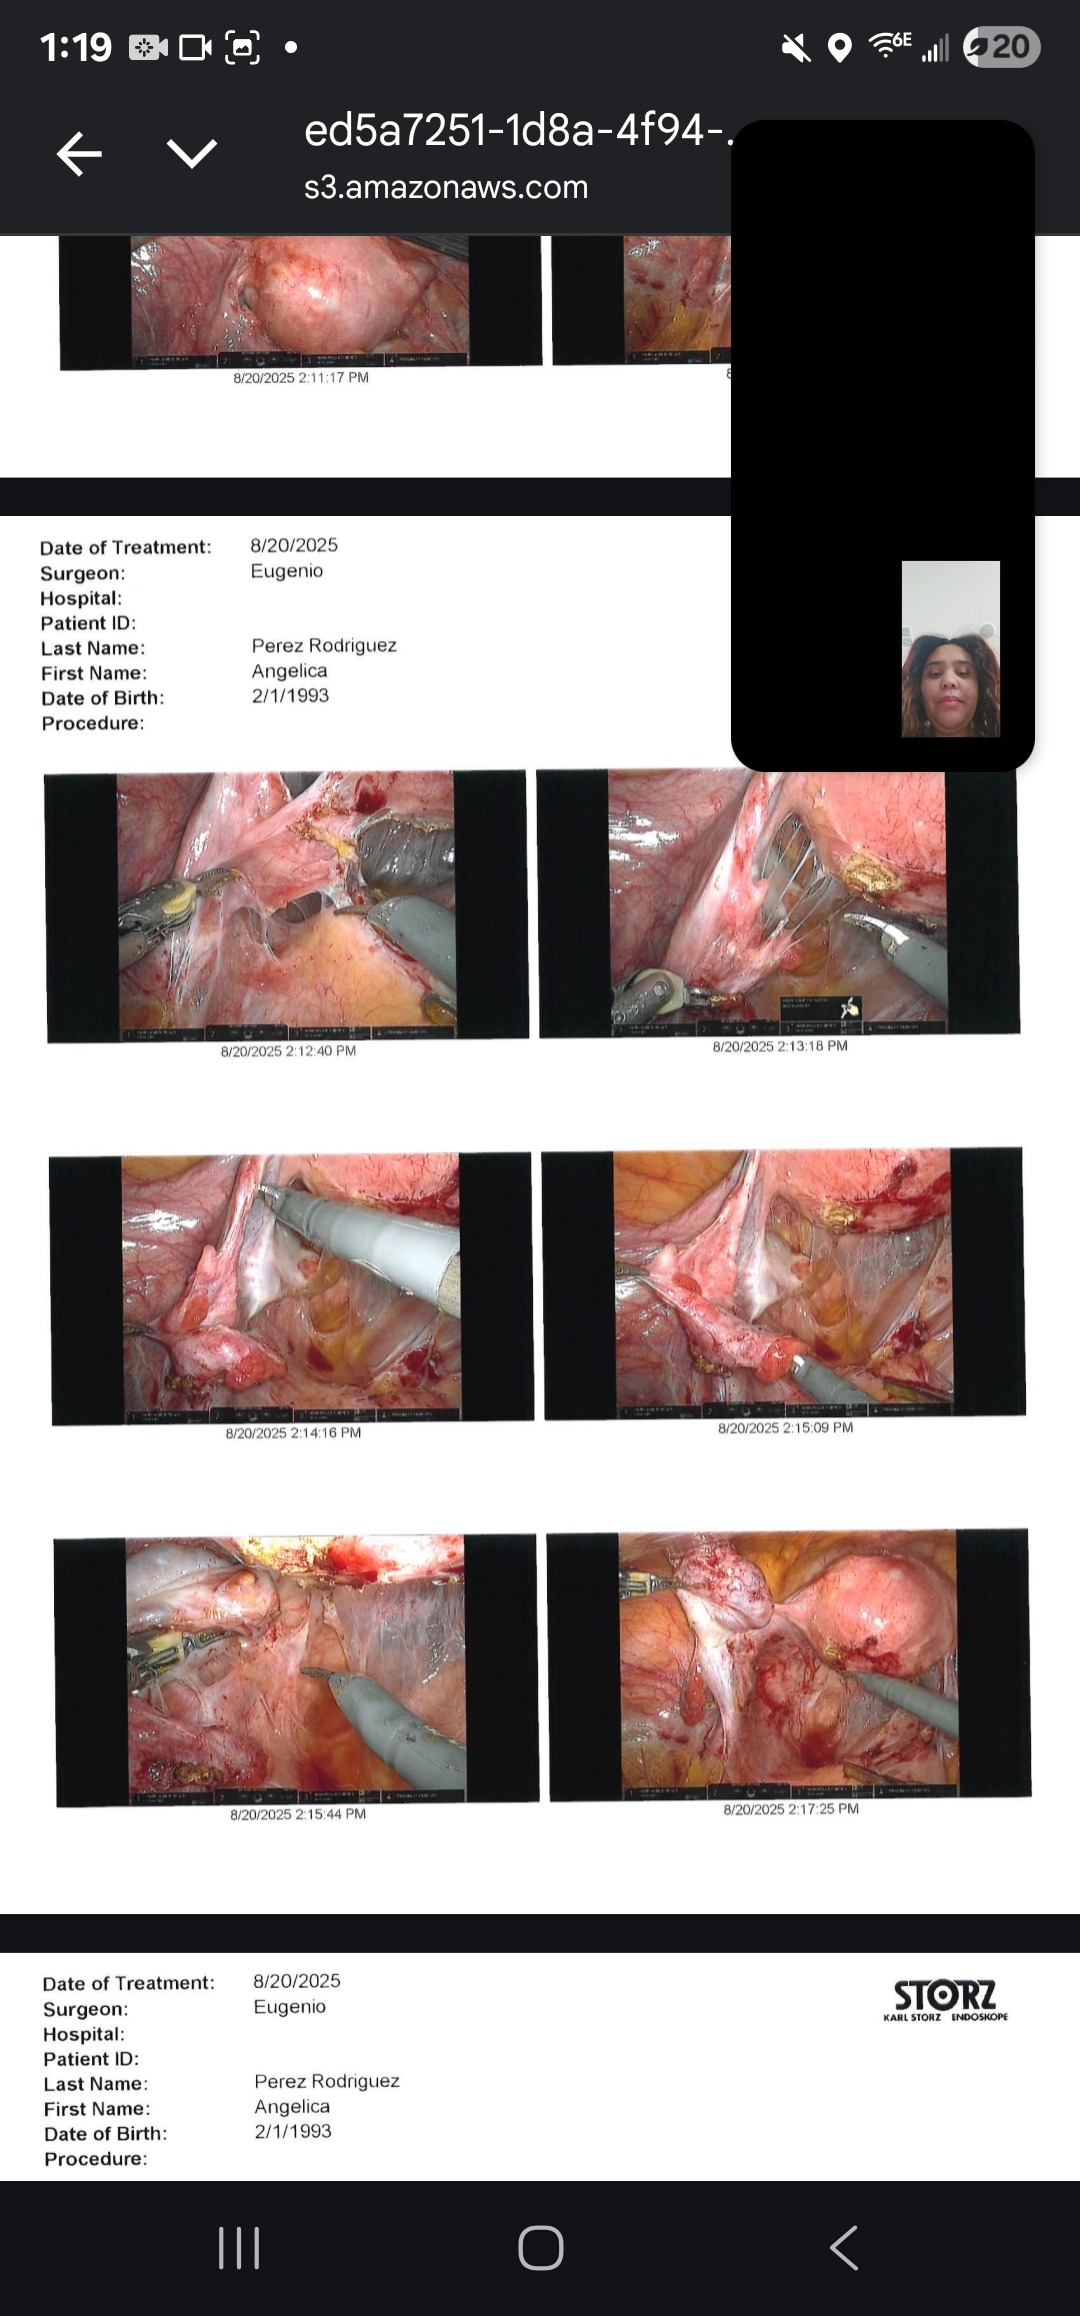

My name is Angelica, and I am fighting Stage 4 deep infiltrative endometriosis. Since 2022, I have gone through 5 surgeries — 3 of them just in the past year. Each operation has been an attempt to ease the pain and give me a chance at a normal life, but the fight is far from over.